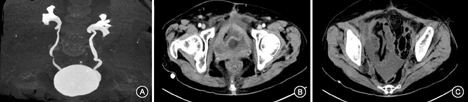

患者女,45岁,因"反复下腹痛2个月"入院。2012年5月22日晨起尝试排尿时突发剧烈下腹部胀痛,伴恶心、呕吐胃内容物、大汗和排尿困难,持续不缓解,有排气排便。外院查体提示下腹部肌紧张、压痛、反跳痛。查血白细胞10.92×109/L,血红蛋白、血小板正常,白蛋白36.5 g/L,血肌酐、淀粉酶正常。腹部超声示腹腔游离液体,最深约8 cm,可见絮状回声。腹盆腔CT示腹盆腔内高密度液体影积聚,CT值在60~63 HU,考虑出血可能,双侧输尿管节段性扩张积水。5月24日腹腔穿刺抽出淡黄色腹腔积液100 ml,腹腔积液比重1.019,细胞总数3 600/μl,白细胞1 060/μl,多核80%,总蛋白8.5 g/L,葡萄糖10.2 mmol/L,氯化物110 mmol/L,病原学检查阴性。5月25日进展至全腹痛,伴嗜睡、血压下降、少尿,予胃肠减压、导尿、补液扩容及哌拉西林/三唑巴坦治疗后好转。6月5日腹部超声未见腹盆腔积液。6月25日再次出现下腹痛、恶心、呕吐,腹部超声示腹腔积液,最深4.3 cm。3 d后复查腹部超声示腹腔内可见大量液性暗区,最大液平10.8 cm。腹部CT:腹腔积液,膀胱充盈饱满及膀胱壁厚薄不均,最厚约0.5 cm,其内密度不均,其后方亦见弧形低密度影,双侧输尿管略宽。予导尿,首次引流出900 ml清亮尿液后下腹胀减轻,同时予补液及抗生素治疗,并放置腹腔引流管后引流清亮腹腔积液,每日引流500~2 000 ml,腹腔积液蛋白8.5 g/L,腹腔积液涂片可见大量增生间皮细胞及少量中性粒细胞。患者症状逐渐好转。既往史:2004年行宫颈癌根治术及术后放化疗,2011年5月复查腹盆超声未见腹腔积液。2005年曾诊为"放射性直肠炎"。2010年因"双下肢麻木、无力"、肌电图提示周围神经病变,诊为"放射性周围神经病",服神经营养药物后好转。2012年7月22日收入我院后:查血常规和粪常规+潜血正常,血白蛋白35 g/L,血清肌酐30 μmol/L,糖类抗原(CA)125 77 800 U/L,CA199、血清癌胚抗原正常。淋巴细胞培养+干扰素测定阴性。心脏超声未见明显异常。PET/CT:宫颈癌术后,放化疗后,未见肿瘤转移、复发证据。CT尿路成像示膀胱壁不均匀增厚,形态欠规整;排泄期膀胱体积明显增大;盆腔内可见多发液性低密度影(图1)。入院后予导尿并持续开放引流,定期更换输尿管;1周后因行妇科超声夹闭导尿管2 h后再发下腹胀痛、恶心、出汗,伴发热,体温最高38 ℃。查体示全腹压痛,右中下腹肌紧张、反跳痛。尿管开放引流出淡黄清亮尿液约220 ml后出现肉眼血尿。急查腹部超声示腹腔可见游离积液,最深8.2 cm。腹腔穿刺引流术引流约50 ml淡黄色浑浊腹腔积液,查腹腔积液比重1.028,细胞总数3 000×106/L,白细胞总数1 850×106/L,多核90%,白蛋白26 g/L,腺苷脱氨酶11.4 U/L,三酰甘油0.33 mmol/L,肌酐37 μmol/L,细菌培养、结核培养均阴性。综合考虑"尿源性腹腔积液、急性腹膜炎"。予保持尿管持续开放、抗生素治疗,患者症状逐渐缓解。经泌尿外科、神经内科和妇科会诊后考虑"神经源性膀胱、膀胱破裂可能性大",建议病情稳定后行膀胱造影、尿动力学检查。出院后患者未规律随诊,每次拔除尿管一段时间后会再次出现上述症状,导尿、抗感染治疗后好转。2014年患者宫颈癌复发,接受规律化疗。2014年5月行膀胱造影可见造影剂经膀胱外溢进入腹腔;术后出现下腹痛、恶心、呕吐及低热,保守治疗后好转。患者拒绝手术治疗,要求长期带尿管,定期更换。最后诊断"自发性膀胱破裂,膀胱腹膜瘘,尿源性急性腹膜炎"。

患者存在明确的膀胱结构改变、功能异常,多次CT提示膀胱壁厚薄不均、形态欠规整,排泄后膀胱体积仍明显增大,且有明确的尿潴留史(自主排尿后单次导尿量竟达900 ml)。患者反复发作的腹膜炎与排尿密切相关:首先,几次明确的腹膜炎发作诱因分别是排尿时、夹闭尿管2 h后及膀胱造影。其次,持续的尿液引流有利于腹膜炎的缓解。再次,最直接的证据是在随访中行膀胱造影可见造影剂漏入腹腔,并诱发急性腹膜炎。另结合前述腹水肌酐>血肌酐,综合考虑膀胱腹膜瘘、尿源性急性腹膜炎、尿源性腹水诊断明确,病初为自发性膀胱破裂基本可诊断。

膀胱破裂的诊断往往比较困难,主要是因为症状不典型、疾病发病率低、医师对该病认识不足,特别是缺乏明确外伤或已知膀胱疾病时。起病可仅表现为腹胀、腹腔积液,也可以剧烈下腹痛、全腹痛为表现,亦可以表现为尿量减少、排尿困难、肉眼血尿和肾功能衰竭。腹腔积液肌酐∶血清肌酐>1有助于尿源性腹水的诊断[2]。膀胱影像学检查特别是增强CT检查有助于疾病的诊断,可出现增强造影剂进入腹腔,游离腹腔气体,膀胱结构异常。膀胱造影检查有助于明确有无膀胱破损[7]。排尿动力学检查及肛周肌电图检查有助于神经源性膀胱的诊断。对于高度怀疑膀胱破裂的患者进行手术探查也有助于该病的确诊。